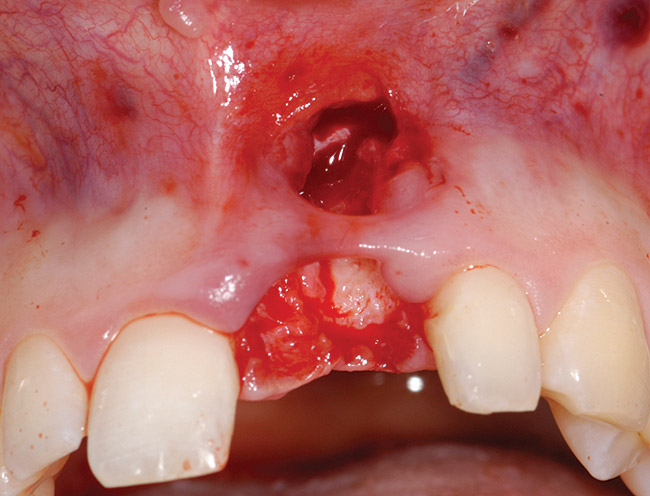

A 54-year-old woman was referred for treatment of a fractured maxillary right lateral incisor, secondary to recurrent subgingival decay. Clinical and radiographic examination revealed a high smile line; a thin, highly scalloped biotype; class II deep bite; a thin labial plate (< 2mm) with 4 mm of vertical bone loss; and class I interproximal height of bone24 (Figure 9 and Figure 10).

Figure 9  Failing maxillary right lateral incisor with root fracture and subgingival caries.

Figure 9

Figure 10  Periapical radiograph of the maxillary right lateral incisor with root fracture.

Figure 10